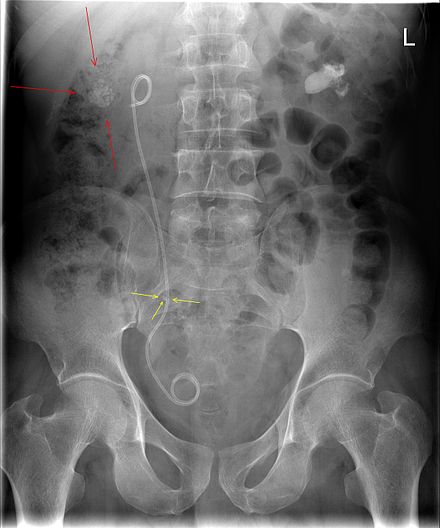

<br />تتعدد طرق تفتيت حصى الكلى المتبعة، ومن أبرز وأهم طرق تفتيت حصى الكلى <br />• تفتيت حصى الكلى بالموجات التصادمية (Shock wave lithotripsy- SWL) <br />يعتبر تفتيت حصى الكلى بالموجات التصادمية من الطرق الأكثر شيوعًا، وتعمل هذه الطريقة بشكل أفضل مع الأحجار الصغيرة أو المتوسطة، وهي طريقة غير جراحية، أي لا تحتاج لإجراء أي جروح في الجلد لتفتيت الحصوات، وعادةً ما يتم هذا الإجراء من خلال اتباع الاتي:<br />1. يعطى المريض مسكنًا خفيفًا للألم.<br />2. يستلقي على طاولة ويستخدم الطبيب الأشعة السينية أو الموجات فوق الصوتية لتحديد موقع الحصوات في الكلية بشكل دقيق.<br />3. يتم تصويب موجات صدمة عالية الطاقة في الكلية من الخارج، وتمر هذه الموجات عبر البشرة لتقوم بتفتيت الحجر إلى قطع صغيرة.<br />قد يضع الطبيب أنبوبًا يسمى الدعامة في الحالب التي تساعد على تفتيت الحجارة، ويستغرق هذا الإجراء حوالي ساعة، وفي أغلب الحالات يعود المريض إلى المنزل في نفس اليوم، ويجب على المريض شرب الكثير من الماء بعد هذا الإجراء لطرد الحصوات عن طريق البول، وقد يضطر المريض للتبول عن طريق مصفاة لالتقاط قطع من الحصوات والتمكن من اختبارها.<br />يمكن أن يحتاج المريض لإعادة الإجراء مرة أخرى في حالة عدم نجاحه في تفتيت الحصوات، وهذا من إحدى الأمثلة على طرق تفتيت حصى الكلى.<br />• تفتيت حصى الكلى بالمنظار<br />يتضمن هذا الإجراء استخدام منظار داخلي لتفتيت الحصوات، وهو عبارة عن أنبوب مرن مزود بضوء وكاميرا ليساعد الطبيب على الرؤية في الداخل، ويتمكن الطبيب من رؤية الحصوات باستخدام المنظار، ويستخدم الليزر في تكسير هذه الحصوات، وقد تستغرق العملية حوالي 30 دقيقة ويمكن لأغلب الحالات العودة إلى المنزل في نفس اليوم.<br />يجب أن تمر قطع الحصوات المفتتة بسهولة عبر البول في الأيام والأسابيع التي تلي هذا الإجراء، ويمكن أيضًا إخراج الحصى عبر الجراحة إن كان تفتيتها صعبًا.<br />• طرق تفتيت حصى الكلى بوصفات طبيعية<br />يمكن أن تساعد بعض الطرق الطبيعية في تفتيت حصى الكلى ، وتشمل طرق تفتيت حصى الكلى الطبيعية الاتي:<br />1. خل التفاح<br />يحتوي خل التفاح على حمض الأسيتيك (Acetic acid) الذي يساعد على إذابة حصى الكلى، كما يمكن أن يساعد خل التفاح في تخفيف الألم الناجم عن الحصوات، وللحصول على فوائد خل التفاح في تفتيت حصوات الكلى يتم إضافة ملعقتين كبيرتين من خل التفاح إلى كوب ماء، وشرب هذا المزيج على مدار اليوم.<br />لا يجب تناول أكثر من كوب واحد من هذا المزيج يوميًا، حيث يمكن أن يسبب مخاطر صحية عديدة، مثل: انخفاض مستويات البوتاسيوم، وهشاشة العظام، ويمكن إضافة خل التفاح إلى السلطات المختلفة، كما يجب على مريض السكري مراقبة مستويات السكر في الدم عند تناوله لهذا المزيج.<br />ينصح بتجنب تناول هذا المزيج في حالة تناول الأنسولين، أو الأدوية المدرة للبول، أو أدوية علاج فشل القلب الاحتقاني.<br />2. عصير الليمون<br />يمكن استخدام عصير الليمون في تفتيت حصى الكلى وذلك بعد إضافته إلى الماء حيث يحتوي الليمون على سترات، وهي مادة كيميائية تمنع تكون حصوات الكالسيوم، كما يمكن أن تقوم هذه المادة بتفتيت الحصوات الصغيرة مما يساعد على مرورها بسهولة.<br />يمكن الحصول على نتيجة جيدة بتناول القليل من عصير الليمون ، وقد تكون هناك حاجة إلى تناول قدر كبير منه للحصول على نتيجة أفضل.<br />3. عصير الريحان<br />أيضًا يحتوي عصير الريحان على حمض الأسيتيك الذي يمكن أن يساعد على تفتيت حصوات الكلى وتقليل الألم، كما أن عصير الريحان غني بمضادات الأكسدة التي تعزز صحة الكلى، ويمكن صنع شاي بواسطة أوراق الريحان وتناولها على مدار اليوم، كما يمكن عصر الريحان وتناوله للحصول على فوائده، ولكن ينصح بتجنب تناول عصير الريحان لأكثر من 6 أسابيع متتالية لتفادي الأضرار الاتية:<br />• انخفاض سكر الدم.<br />• انخفاض ضغط الدم.<br />• زيادة النزيف.<br />